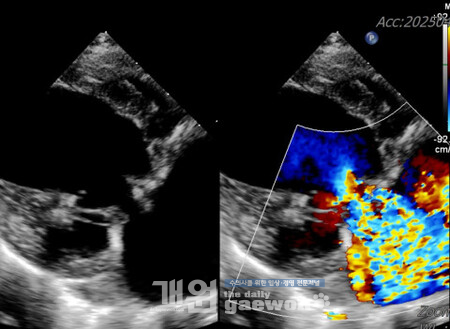

해당 환자는 8세, 6.2kg의 스피츠로 단백소실성장병증(Protein-Losing Enteropathy, PLE)을 앓고 있었으며, 장기 항생제 치료 이력이 있는 고위험 환자였다. 1차 수술에서는 점액종성 변화로 변성된 판막을 재건해 역류를 현저히 개선했고, 이후 약물 없이 안정적인 회복을 보였다. 하지만 수술 약 4주 후 판막에 세균 감염이 발생했고, 정밀 검사 결과 다제내성균인 엔테로코커스 페시움(Enterococcus faecium)에 의한 감염성 심내막염으로 확인, 장기 항생제 치료와 장염으로 인한 장벽 손상이 원인으로 지목됐다. 의료진은 6주간 정맥 항생제 치료로 감염을 통제했지만 판막 구조 손상이 심각해 재수술이 결정됐다.

2차 수술에서는 감염으로 짧아진 승모판막 전엽을 소 심낭 패치로 연장하고 재건하는 전엽 패치 증강술(anterior mitral valve leaflet patch augmentation)을 적용했다. 이는 사람 심장 수술에서 활용되는 고난도 기법으로 개에게 적용된 것은 처음이다. 9시간에 걸친 수술 이후 환자는 모든 심장약과 이뇨제를 중단할 수 있었고, 재수술 3개월이 지난 현재까지 기절 증상 없이 정상적인 생활을 이어가고 있다. 감염성 심내막염을 앓은 개의 평균 생존 기간이 약 70일인 점을 고려하면, 발병 후 10개월 이상 생존하며 호전 중인 이번 사례는 수술적 치료의 가능성을 입증한 중요한 사례로 평가된다.